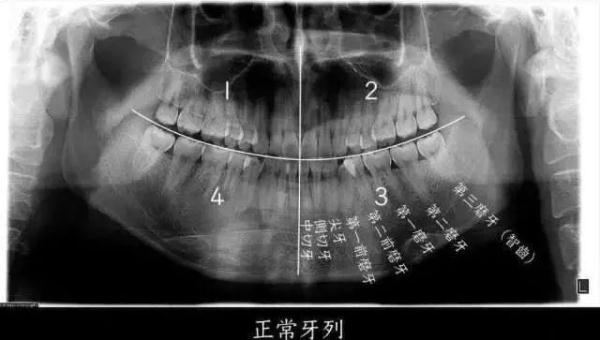

▲ 智齿即第三磨牙,位于口腔最远最深位置

图源:浙江大学医学院附属第二医院何剑亮医生

如果把一个正常成年人的口腔分为左上、左下、右上、右下四个区域的话,每个区域会有 8 个牙齿,长在最后的第8颗牙齿,就是我们口中的“智齿”,即第三磨牙。